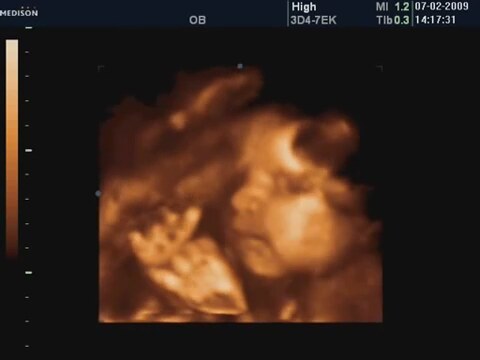

28 Haftalık Bebeğin 4 Boyutlu Ultrasın Görüntüsü